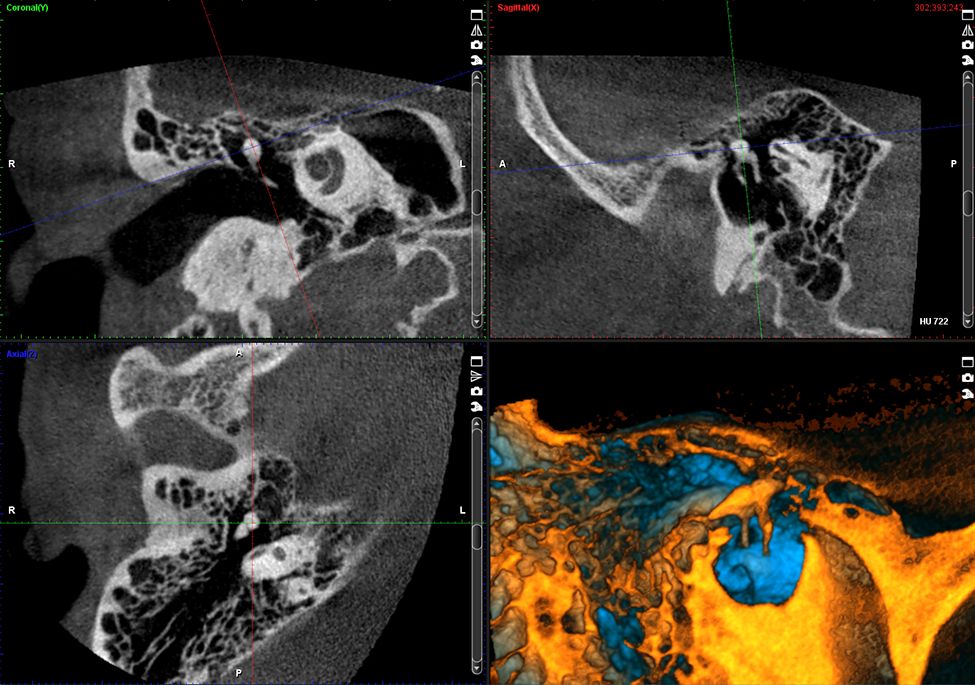

Zaawansowane obrazowanie TMJ

Unit Planmeca ProMax 3D Plus obsługuje woksele w rozmiarach od 600 do 75 μm, natomiast oprogramowanie Planmeca Romexis® oferuje wszechstronne narzędzia do wizualizacji dróg oddechowych, zatok, tkanek miękkich, a nawet najmniejszych struktur kostnych uszu.

Obrazy Kliniczne Planmeca ProMax 3D Plus